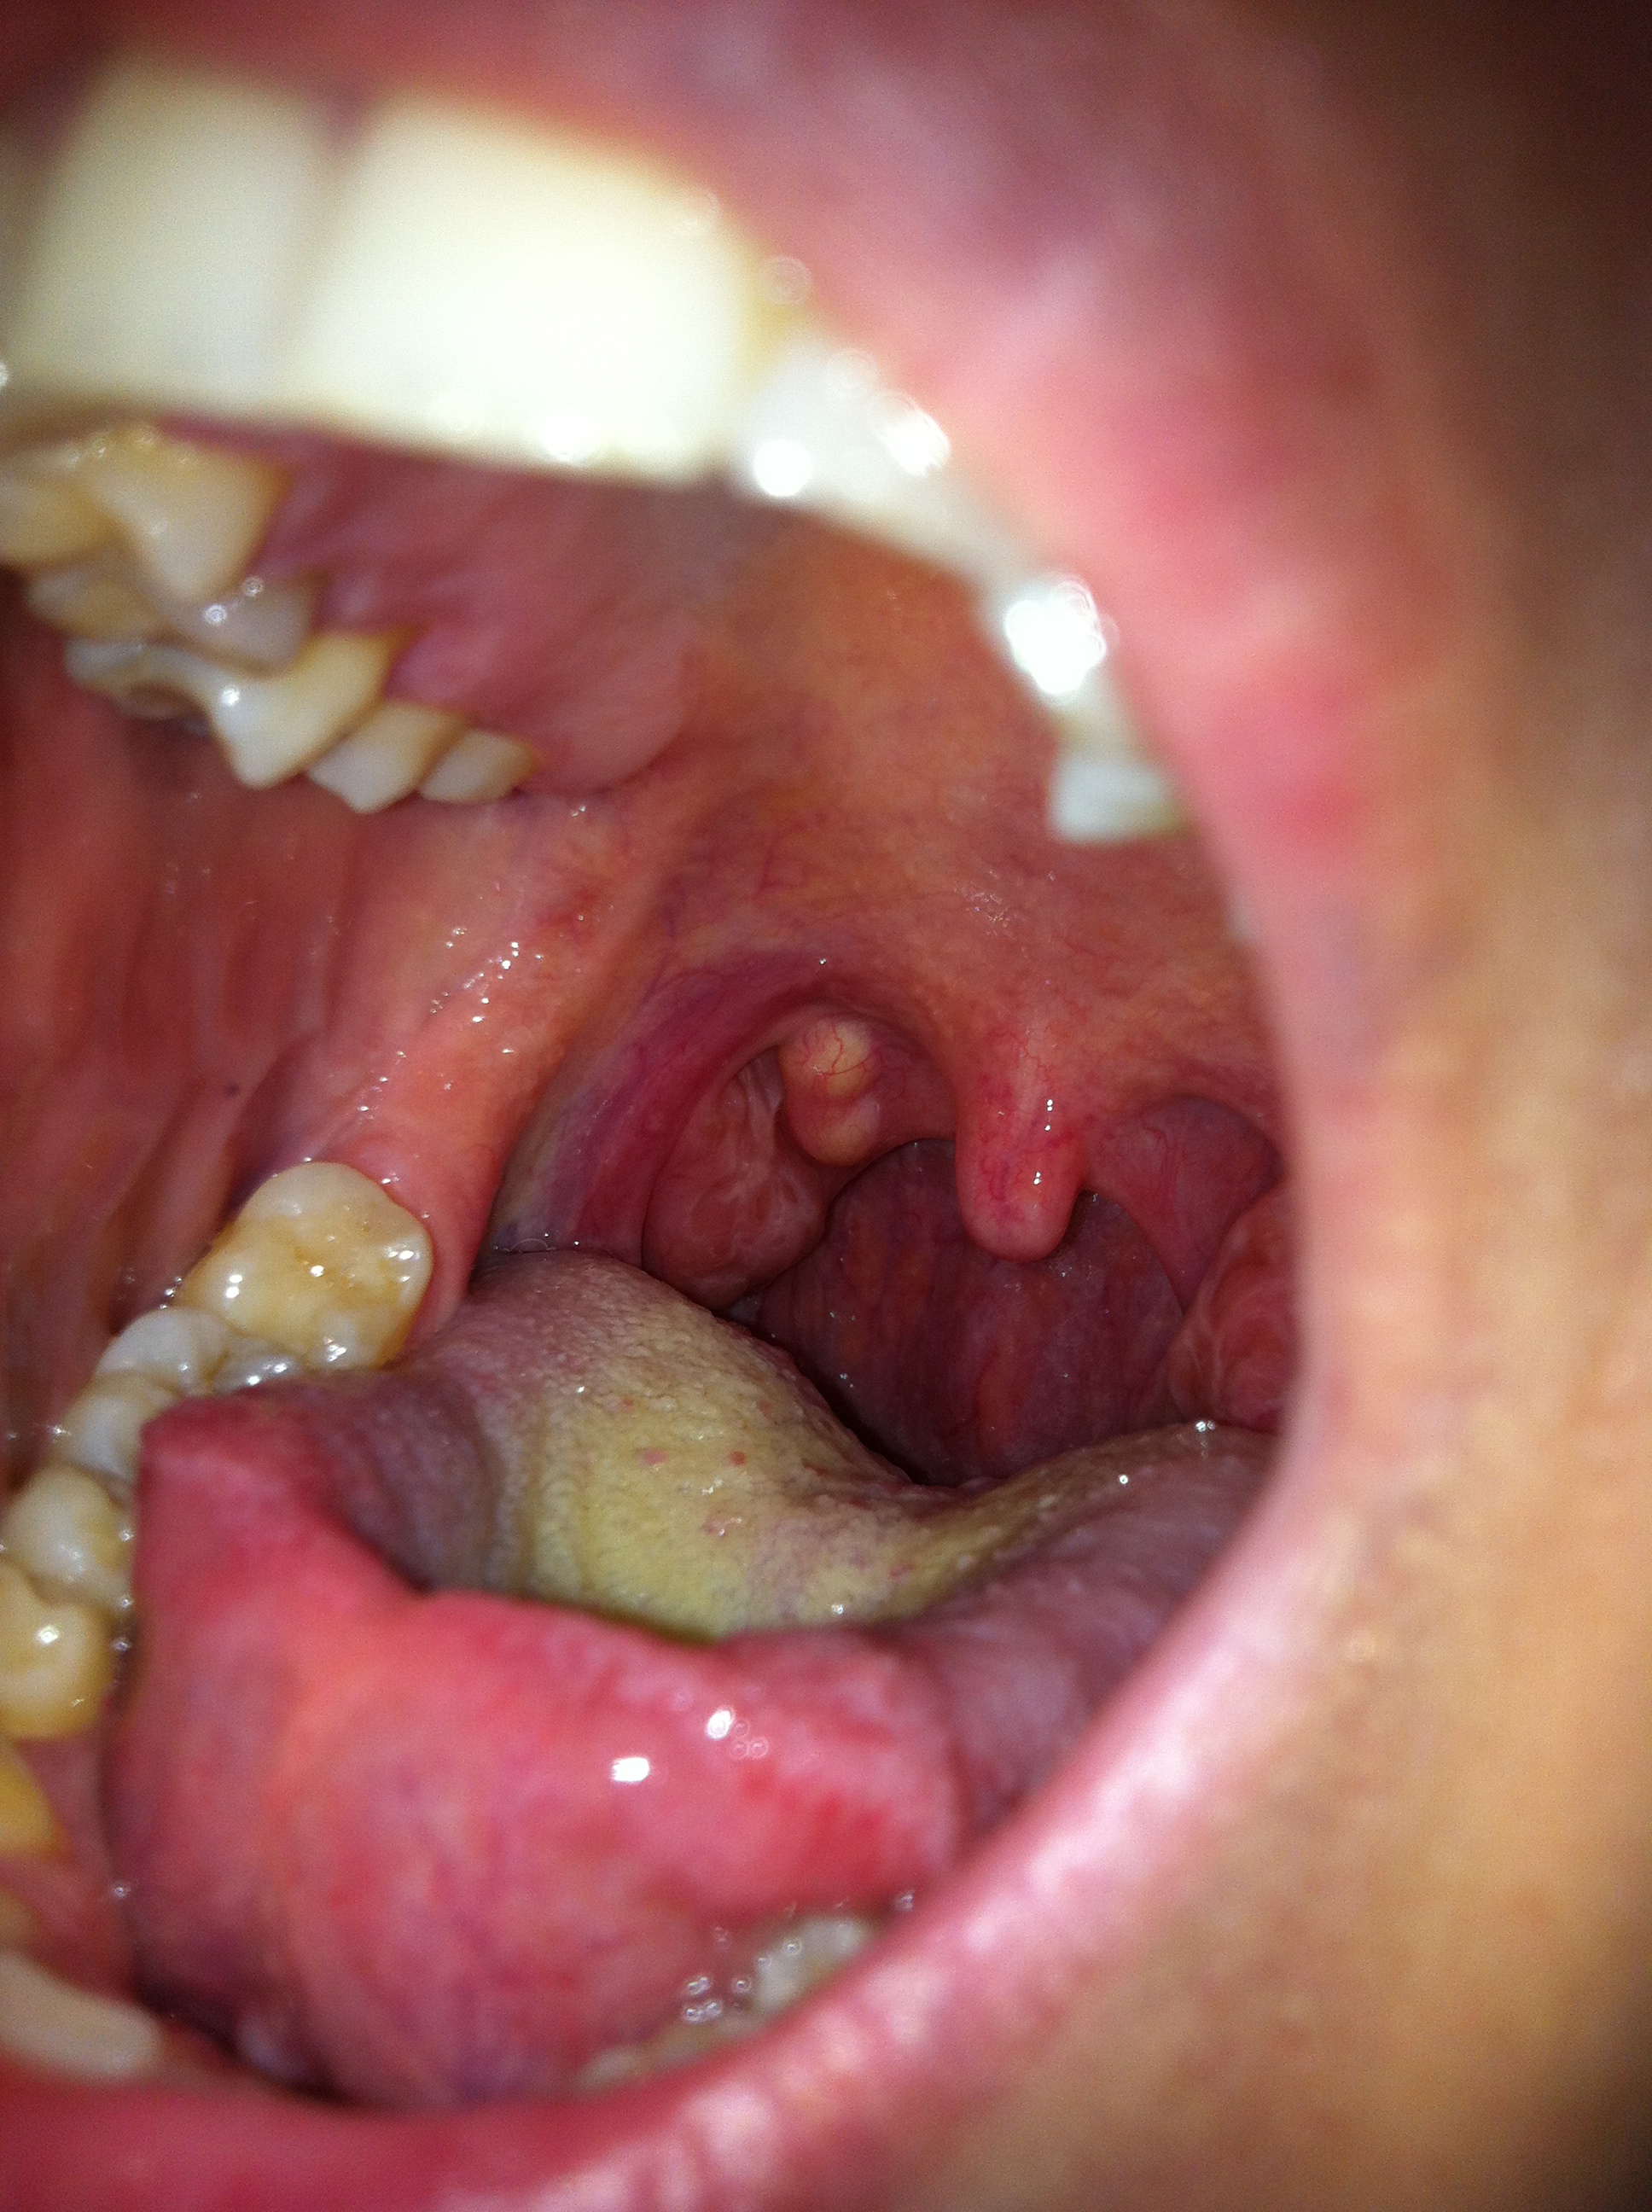

salve dottore, premetto che sono una ragazza che da sempre sono soggetta a tonsilliti con placche.. ho curato il mio mal di gola con augmentin per bocca, dopo aver consultato il mio medico di famiglia. Dopo circa 5 giorni il dolore è quasi svanito. mi sono resa conto pero che vicino alla tonsilla destra, ancora non completamente guarita dal gonfiore, si sono formate due bolle molto evidenti di colore bianco/giallastro che nn ho mai notato prima. ho gia consultato un medico otorinolaringoiatra il qualche non mi ha saputo spiegare ancora la loro origine, mi ha pero fatto fare delle analisi del sangue (emocromo,pcr, mononucleosi, fattore reumatico,ves, tas) risultato ancora in corso.. sono molto preoccupata, mi sa dire secondo lei da cosa potrebbero dipendere o cos altro devo fare??

N.B. ho allegato anche una foto!

Da quello che descrive e dalla foto... Direi di non preoccuparsi troppo... Sembrerebbero due piccole cisti da ritenzione mucosa (cisti formatasi da una cellula mucipara o ghiandola salivare).... Gli esami le sono stati richiesti per avere un quadro della situazione tonsillare generale....

Ovviamente poi via web non e' semplice e le consiglio di affidarsi al collega.... Però ribadisco...stia tranquilla